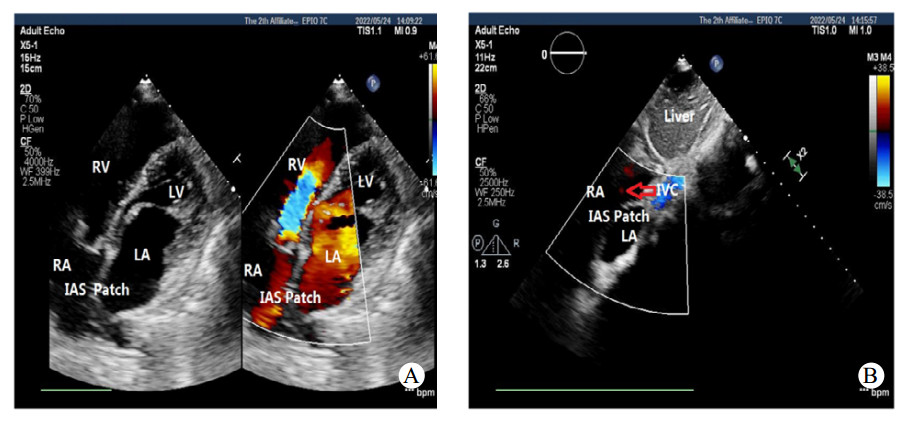

1 资料与方法患者,男性,21岁,于2022年5月18日收治本院,无明显不适主诉,15年前体检时发现ASD,长期门诊随访。患者近期门诊随访时外院心脏超声提示:房间隔缺损(继发孔型),右心增大,肺动脉增宽,轻度肺动脉高压(肺动脉平均压33 mmHg,1 mmHg=0.133 kPa),考虑患者房间隔缺损,存在手术指征,建议手术治疗,门诊以“房间隔缺损”收住入院。入院时查体:神志清楚,体温: 37.2℃,脉搏: 73次/min,血压: 109/66 mmHg,口唇无发绀,可见杵状指,颈静脉无怒张,双肺呼吸音清,未闻及明显干湿啰音,心律不齐,肺动脉瓣听诊区可闻及收缩期杂音,腹软,无压痛及反跳痛,肝脾肋下未及,双侧肾区无明显叩痛,脊柱侧弯,双下肢无水肿,神经系统检查阴性。血气分析氧分压:57 mmHg,血氧饱和度:88.7%,血、尿常规、生化、凝血项无殊。本院经胸心脏超声提示:先天性心脏病, 巨大房间隔缺损合并下腔静脉回流入左房(右向左分流),右心增大,轻度肺动脉高压,估测肺动脉收缩压(pulmonary artery systolic pressure,PASP)40 mmHg(图 1)。胸部高分辨CT平扫提示:心脏饱满,提示肺静脉异常引流,房间隔缺损可能,建议增强(图 2)。术前诊断:先天性心脏病:巨大房间隔缺损(下腔静脉侧及房顶部无房间隔残留组织),轻度肺动脉高压,完全性右束支传导阻滞,脊柱侧弯,胆囊内息肉。根据术前检查,决定进行心脏不停跳房缺修补术(人造补片)以及三尖瓣成形术。全麻后,沿胸骨正中切口开胸,切开右心房,术中所见:右心明显增大,房间隔缺损,下腔静脉无残端,大小约4.0 cm×5.0 cm,三尖瓣瓣环增大,约43 mm, 少量反流,未见肺静脉异位引流、室间隔缺损、动脉导管未闭、下腔静脉异位引流等心内其他畸形。手术体外循环下不停跳牛心包补片修补房缺,三尖瓣成形、置入28# SORIN成形环一枚(图 3)。术程顺利,术后即刻经食道超声未见房间隔明显残余分流,三尖瓣未见明显反流。心电图示窦性心律。术后给与头孢呋辛钠预防感染,护胃、化痰、利尿等对症支持治疗。术后经胸心脏超声提示:房间隔缺损修补术后,房水平未见残余分流,三尖瓣成形术后(图 4)。手术前后左心功能未见明显异常(表 1)。经1周治疗后,患者恢复良好,血气分析氧分压:141 mmHg,血氧饱和度:99.9%,予带药出院。

| A: 四腔心切面显示房间隔补片样回声,未见房水平分流;B:修补术后,下腔静脉血回流入右房。LA: 左房;RA: 右房;LV: 左室;RV:右室;IAS:房间隔补片 图 4 患者术后经胸心脏超声表现 |